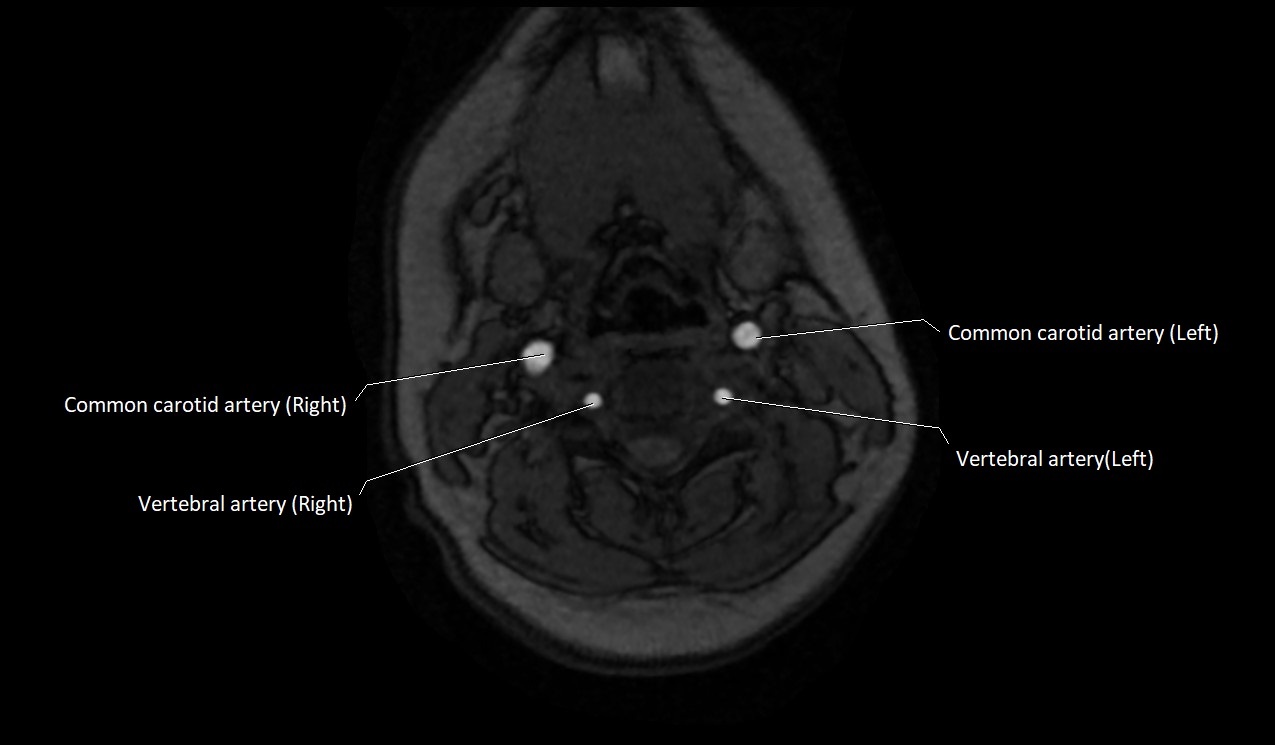

MRI Appearance:

• T1-Weighted Images:

• Appears as a tubular, hypointense (dark) structure relative to muscle

• May show flow void if the blood flow is fast

• T2-Weighted Images:

• Typically hypointense or isointense to muscle, but can be hyperintense if slow flow or stasis is present

MRI images